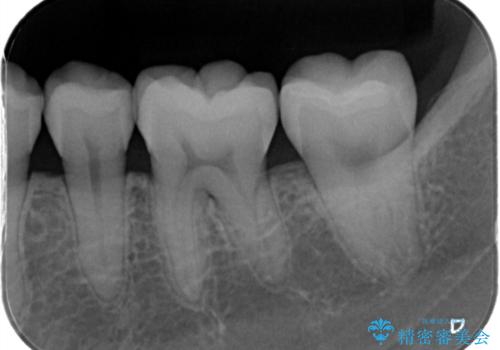

- 銀歯が気になるためやり替えたいとのことで来院されました。

セラミックインレーで治療を行いました。

口の中にチラつく銀歯は適合の良いセラミックインレーでやり替えることで綺麗にやり替えることができます。